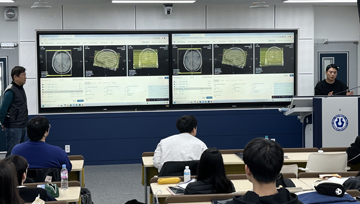

2) MRI 시뮬레이터

의료영상기법으로 적용되는 자기공명영상물리학은 정상인 및 질환에 대한 신체의 생리학적 과정을 해부학적으로 영상화 할 수 있습니다. 또한 혈관조영 검사법의 목적과 검사 과정을 익히고, 검사 중에 다양하게 변화되는 혈관조영상과 진단과 치료를 병행하는 중재적방사선학을 이해하고 이에 관한 지식을 습득할 수 있는 실습실입니다.

특히 MR 시뮬레이터는 대학교 최초로 최신의 실습 장비로, 학생들에게 실제 임상에서 하는 진단 및 치료를 경험해 볼 수 있고 보다 이해도를 높일 수 있는 실습실입니다.

MRI 시뮬레이터

MRI 시뮬레이터

MRI 시뮬레이터